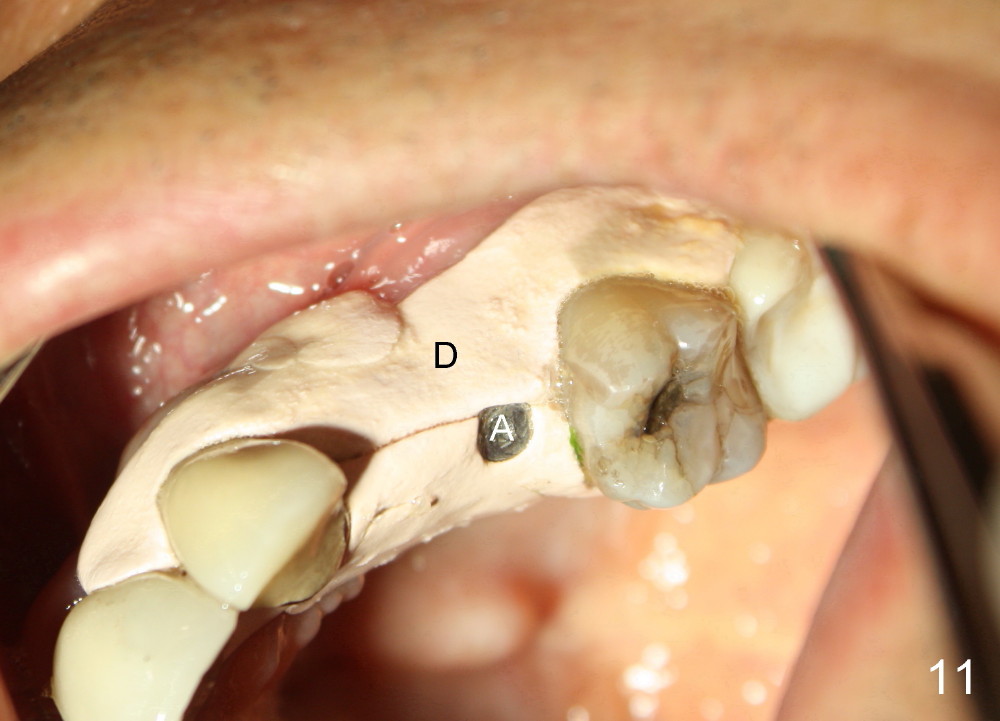

The anterior retainer is kept as a crown at #11 (Fig.2: C), whereas the residual root at the site of #13 is extracted with apical perforation (Fig.3 ^).  It is confirmed by Fig.4 (<).  To close the perforation, an osteotomy is initiated on the palatal wall of the socket with a 2 mm osteotome (Fig.5 insert: circle).  As the osteotomy is being enlarged by a 3 mm osteotome, the bone between the original socket and the osteotomy is being pushed buccally.  The former is being closed (Fig.5).  The osteotomy is finished with combination of osteotomes and reamers.  Fig.6 shows that a 5x14 mm tap is inserted at the site of #13 and that the sinus floor is lifted.  In fact the sinus membrane is partially torn at the osteotomy, which is repaired by insertion of Colla-form Dressing (Impladent), followed by autogenous bone (harvested from reamers) mixed with Osteogen  (Impladent).  A 5x14 mm implant is placed at the site of #13 with insertion torque more than 60 Ncm (Fig.7: I).  An incision is made at the site of #12 to start osteotomy with insertion of a parallel pin (Fig.7 P).  A 3 mm reamer is kept in place for position confirmation (Fig.8 R).  Due to ridge atrophy (Fig.2 arrowheads), a much smaller, but longer implant is placed at the site of #12 (Fig.9: 4x17 mm).  The autogenous bone harvested from #12 osteotomy is placed in the buccal gap of #13, followed by insertion of Colla-form Dressing (Fig.10 M).  To protect the membrane, a short abutment (4x3 mm) is temporarily placed (Fig.9,10 A) and perio dressing (Fig.9 D) is applied around the abutment and the interproximal areas of the neighboring teeth.  Usually perio dressing dislodges around 1 week postop, particularly for a large edentulous space.  In this case, the dressing is quite stable 11 days postop: the abutment (Fig.11 A) appears to contribute to retention of the dressing (D).